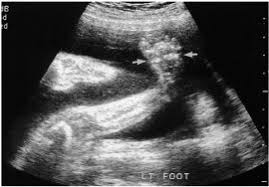

Imaging technique and findings ultrasound. Five cases of congenital clubfoot diagnosed prenatally by ultrasound are reported. Congenital talipes equinovarus is considered the most common anomaly affecting the feet diagnosed on antenatal ultrasound. The addition of microarray studies may increase the yield of invasive prenatal testing, although the complex inheritance patterns of clubfoot suggest that it rarely occurs due to a single gene mutation. 44% of fetuses underwent invasive diagnostic testing. Approximately 10% of all clubfeet can be diagnosed by 13 weeks gestation, and about 80% can be diagnosed by 24 weeks gestation. Although clubfoot is diagnosed at birth, many cases are first detected during a prenatal ultrasound. Ility of the ponseti method in correcting clubfeet; Once the child is born, the condition is clearly visible. Clubfoot can also be diagnosed by a doctor immediately after a baby is born. About 10 percent of clubfeet can be diagnosed as early as 13 weeks into pregnancy. Clubfoot may also result from a restricted environment in utero, such as from prolonged oligohydramnios or with abnormalities of the uterus that limit expansion of the gestational sac. Prenatal diagnosis of clubfoot is made sonographically when the bones of the foot lie in the same planes as the bones of the lower leg (figure 1).

More than 250 genetic syndromes include clubfoot as one component. Commonly associated with prolonged oligohydramnios, brain abnormalities, spina bifida, skeletal and neuromuscular disorders. Prenatal diagnosis of clubfoot is made sonographically when the bones of the foot lie in the same planes as the bones of the lower leg (figure 1). Clubfoot is present in approximately 1 in 1000 live births in the united states. It is observable at birth and ultrasound may be used to diagnose it prenatally. With prenatal ultrasound, parents often learn about clubfoot weeks or months before their child's arrival. Unilateral versus bilateral clubfoot does not affect the risk of chromosomal abnormality. Although clubfoot is diagnosed at birth, many cases are first detected during a prenatal ultrasound. I had a normal nipt and afp. Like about half of children with the condition, the ultrasound showed that cheryl and sue's baby would have clubfeet on both sides. Classification is categorized as complex, where other structural abnormalities are observed or isolated, implying the lack of such anomalies. Clubfoot causes the front of the foot to turn inward and the heel to point down. The incidence of clubfoot may be higher within an affected family and may be associated with other structural anomalies or chromosomal abnormalities.

In a fetus with clubfoot, the long axis of the foot (the sole) and the tibia can be seen in the same plane on ultrasound. However, diagnosis based on ultrasound alone produces a 20% false positive rate. Clubfoot is present in approximately 1 in 1000 live births in the united states. As many as four children out of every 1,000 are born with clubfoot. About 50 percent of children with clubfoot have it in both feet, a condition known as bilateral clubfoot.